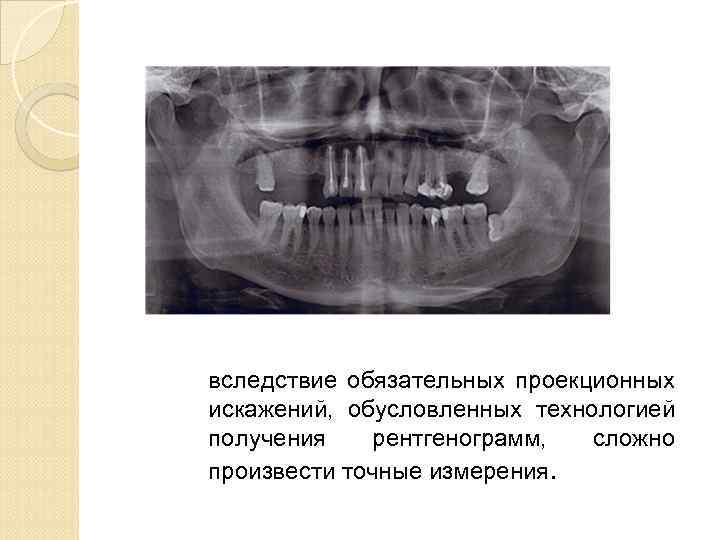

вследствие обязательных проекционных искажений, обусловленных технологией получения рентгенограмм, сложно произвести точные измерения.

вследствие обязательных проекционных искажений, обусловленных технологией получения рентгенограмм, сложно произвести точные измерения.

У пациентов с дефектами зубных рядов при подготовке к имплантации ортопантомограммы не всегда позволяют точно оценить степень атрофии альвеолярных отростков в различных плоскостях, четко рассчитать расстояние от альвеолярного гребня до важных анатомических образований

У пациентов с дефектами зубных рядов при подготовке к имплантации ортопантомограммы не всегда позволяют точно оценить степень атрофии альвеолярных отростков в различных плоскостях, четко рассчитать расстояние от альвеолярного гребня до важных анатомических образований